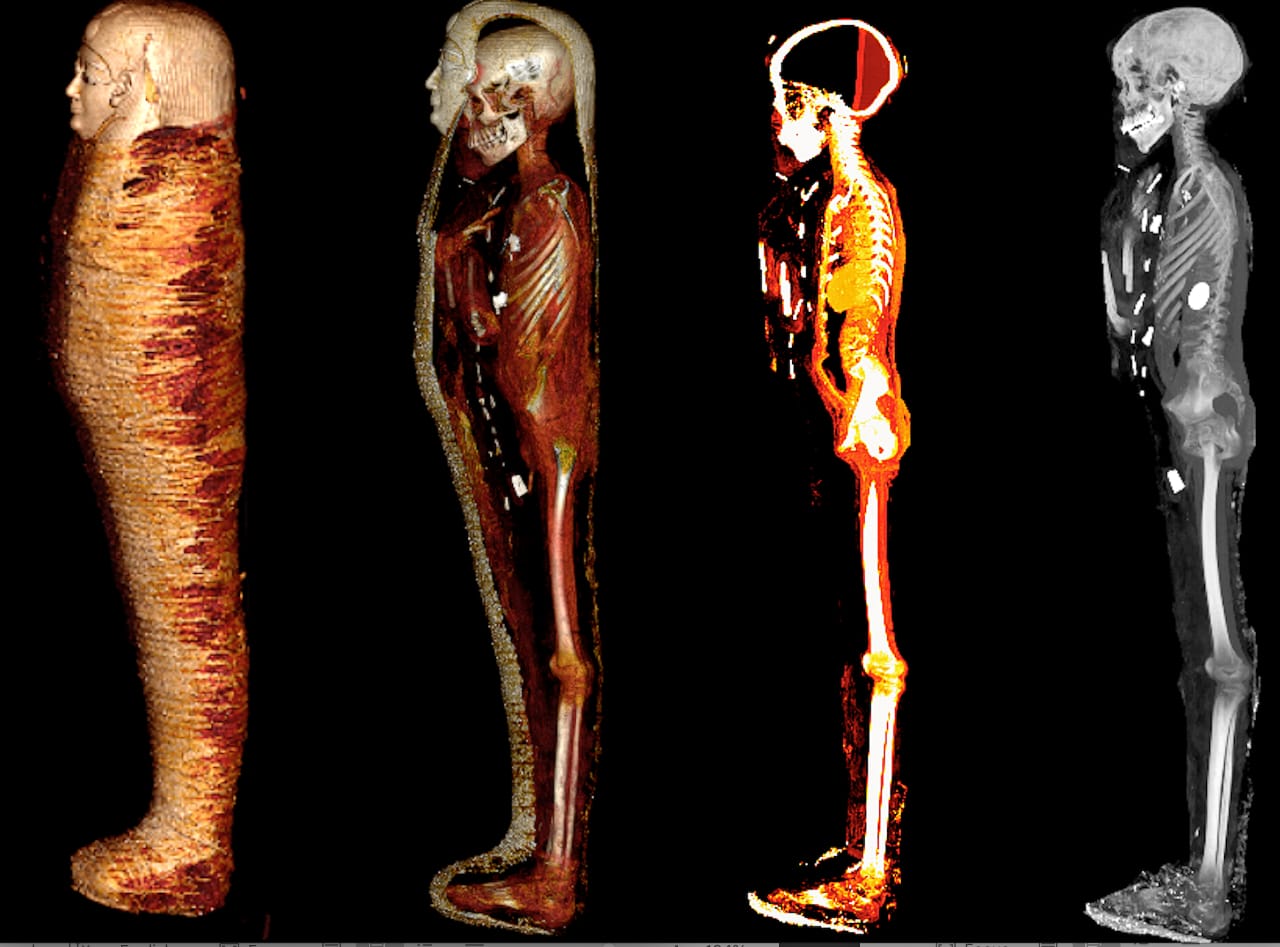

كشفت الأشعة المقطعية والطباعة ثلاثية الأبعاد أسرار مومياء الصبي الذهبي المخزنة في بدروم المتحف المصري بالتحرير لأكثر من قرن من الزمان، وقد تم نشر نتائج هذه الدراسات العلمية بمجلة Frontiers in Medicine اليوم 24 يناير 2023، والتي أسفرت عن الكشف عن هوية هذه المومياء وحالة حفظها وما تحتويه من أسرار.

تم العثور على هذه المومياء ملفوفة بالكامل بالكتان عام 1916، داخل مقبرة من العصر البطلمي (حوالي 300 ق.م.) بمدينة إدفو بمحافظة أسوان حيث تم نقلها وحفظها، آنذاك، ببدروم المتحف المصري بالتحرير دون فحص لأكثر من قرن من الزمان، حتي تم فحصها لأول مرة عام 2015 من قبل الدكتورة سحر سليم أستاذ الأشعة بكلية الطب جامعة القاهرة بالتعاون مع صباح عبد الرازق مدير عام المتحف المصري بالتحرير ومحمود الحلوجي المدير الأسبق للمتحف، باستخدام الأشعة المقطعية، بشكل آمن، من خلال الجهاز الموجود بالمتحف واستخدام الأشعة المتقدمة وبرامج الكمبيوتر الحديثة وكذلك الطباعة ثلاثية الأبعاد.

وأكدت الدكتورة سحر سليم أن الدراسة كشفت عن وجه المومياء لأول مرة بعد إزالة اللفائف بشكل افتراضي بتقنية الأشعة المقطعية، حيث أتاحت الدراسة فرصة فريدة لاكتشاف أسرار تحنيط المومياء دون المساس باللفائف، وكما تركها المصريين القدماء.

وساعد استخدام التكنولوجيا والتقنيات الحديثة في التصوير الطبي بالأشعة ثلاثية الأبعاد في تقديم رؤية قيمة للمومياء، مما دعم قرار إدارة المتحف المصري بالقاهرة لنقل المومياء من بدروم المتحف لعرضها داخل قاعات العرض به، حيث لقبت بـ "مومياء الصبي الذهبي".